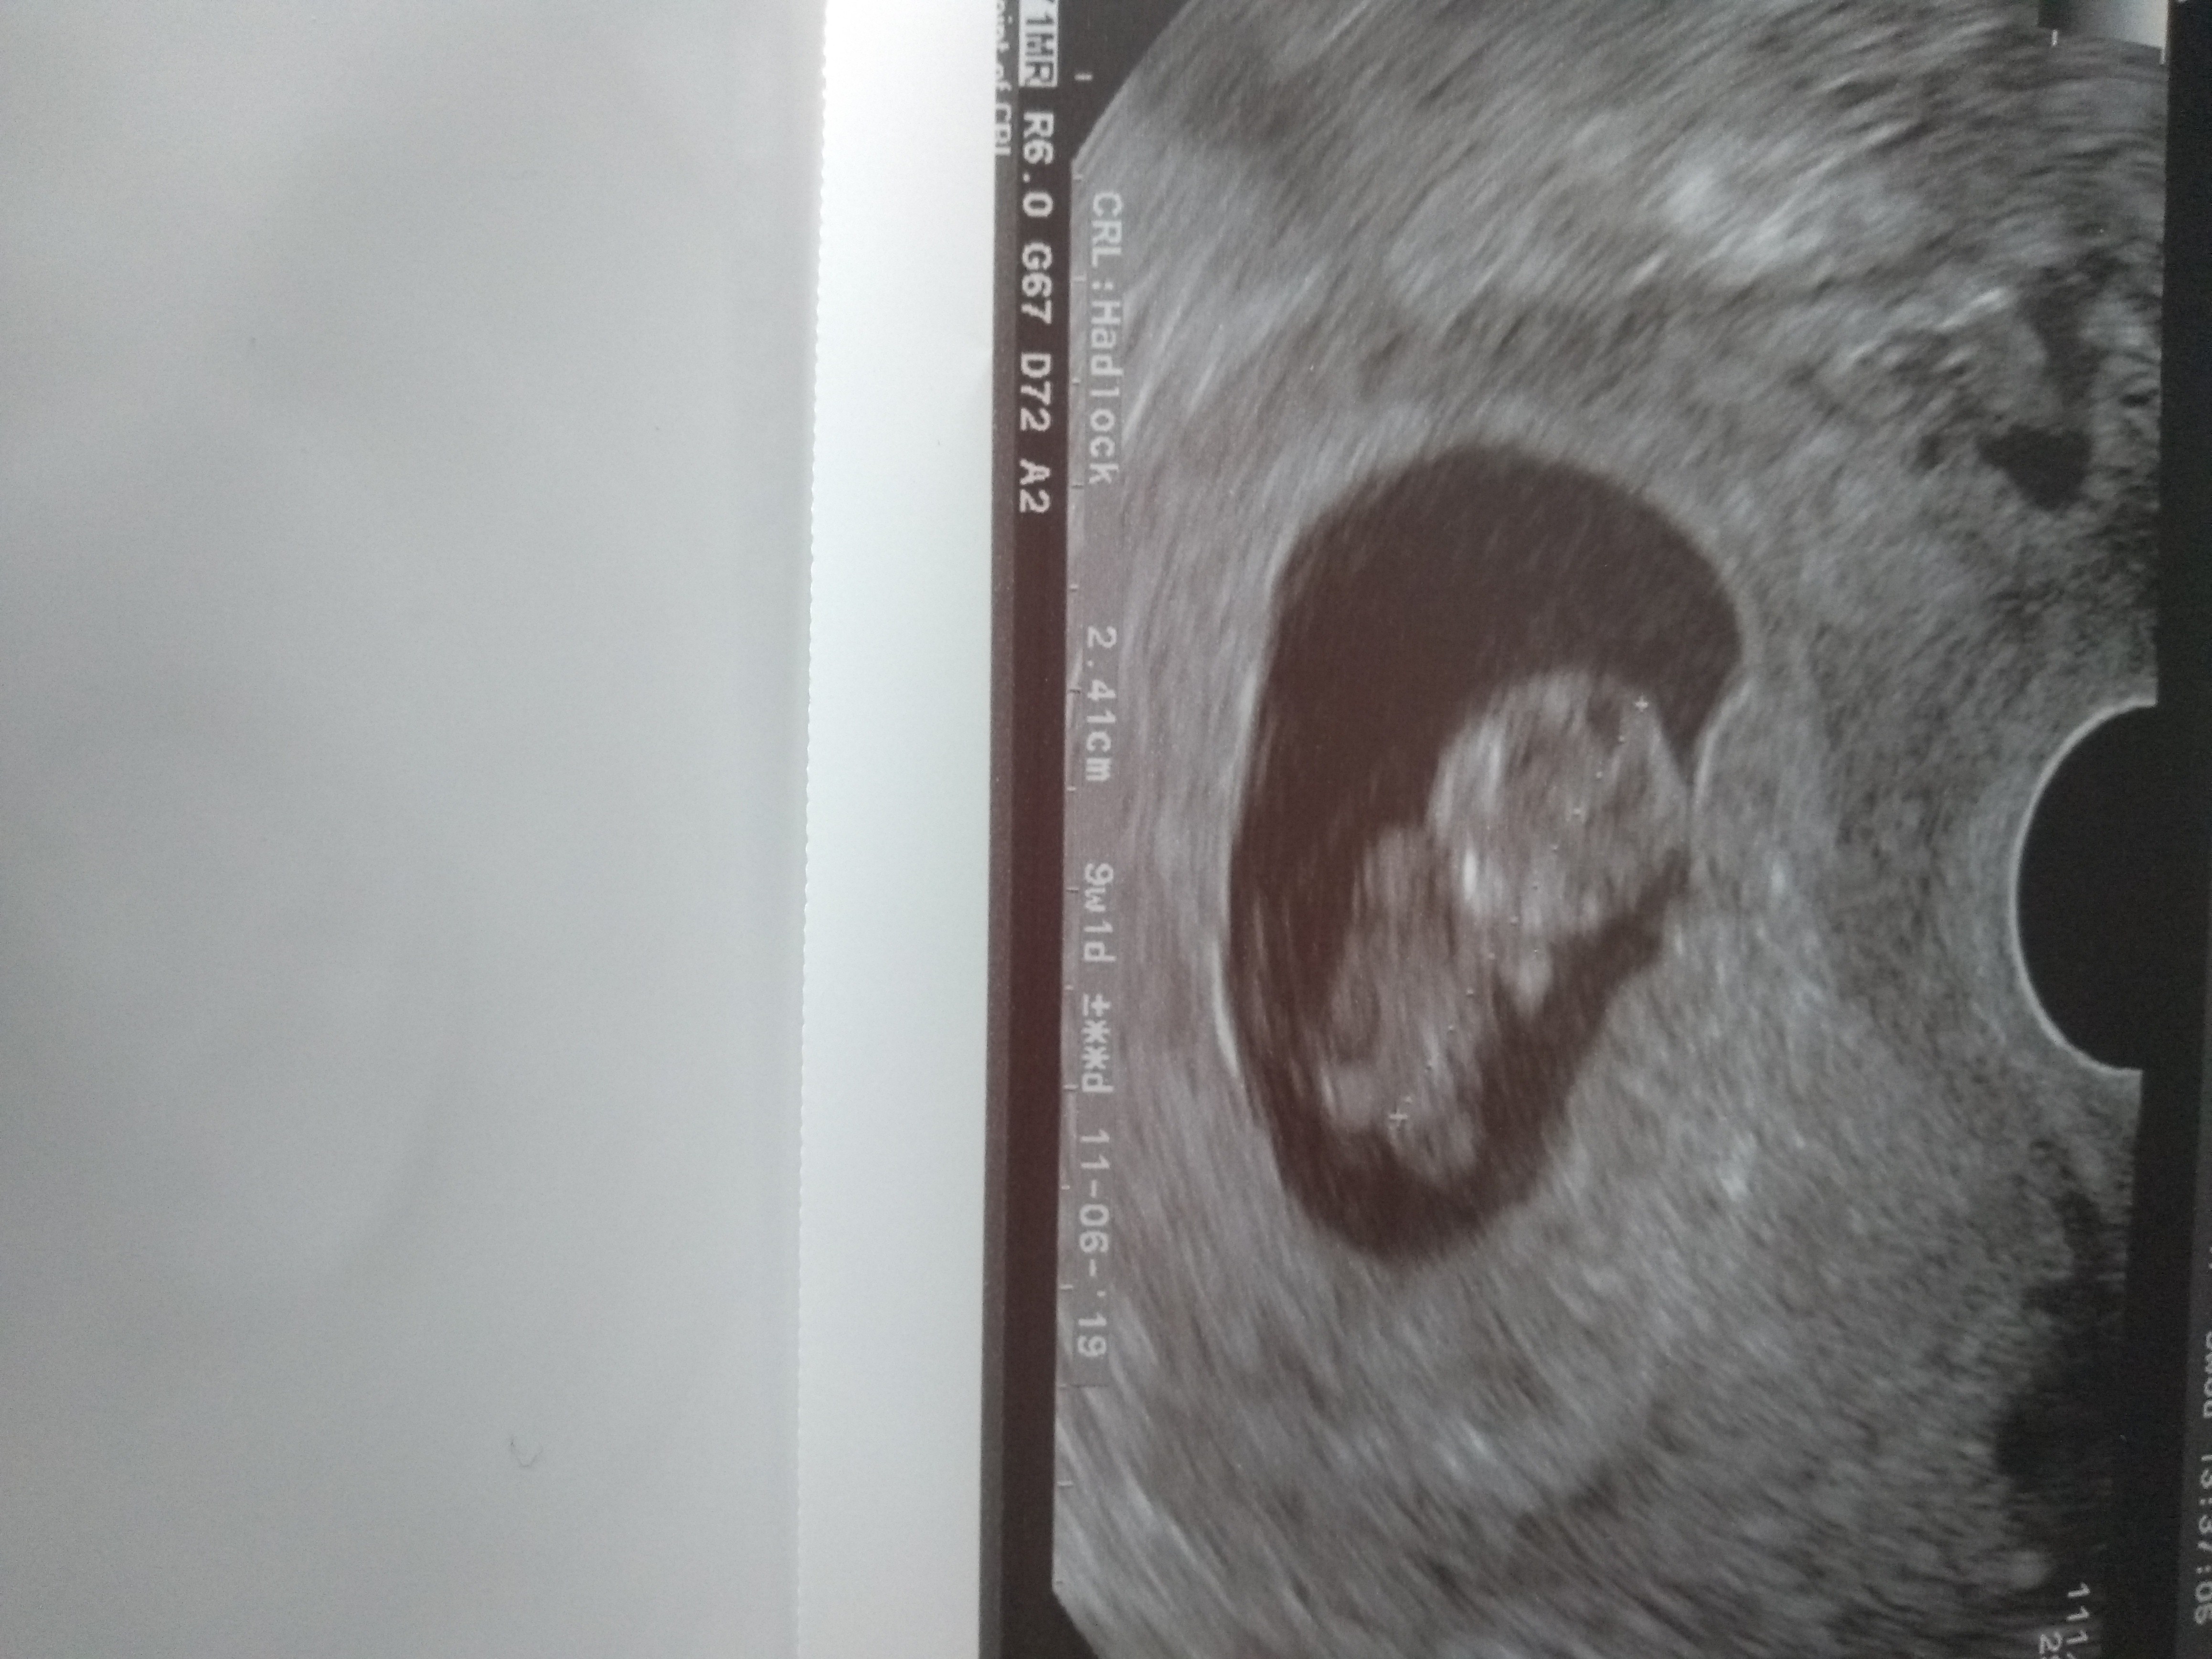

Dopiero co widziałam nasze bobo a patrząc na Wasze zdjęcia juz nie mogę sie doczekac kolejnego badania[emoji6]